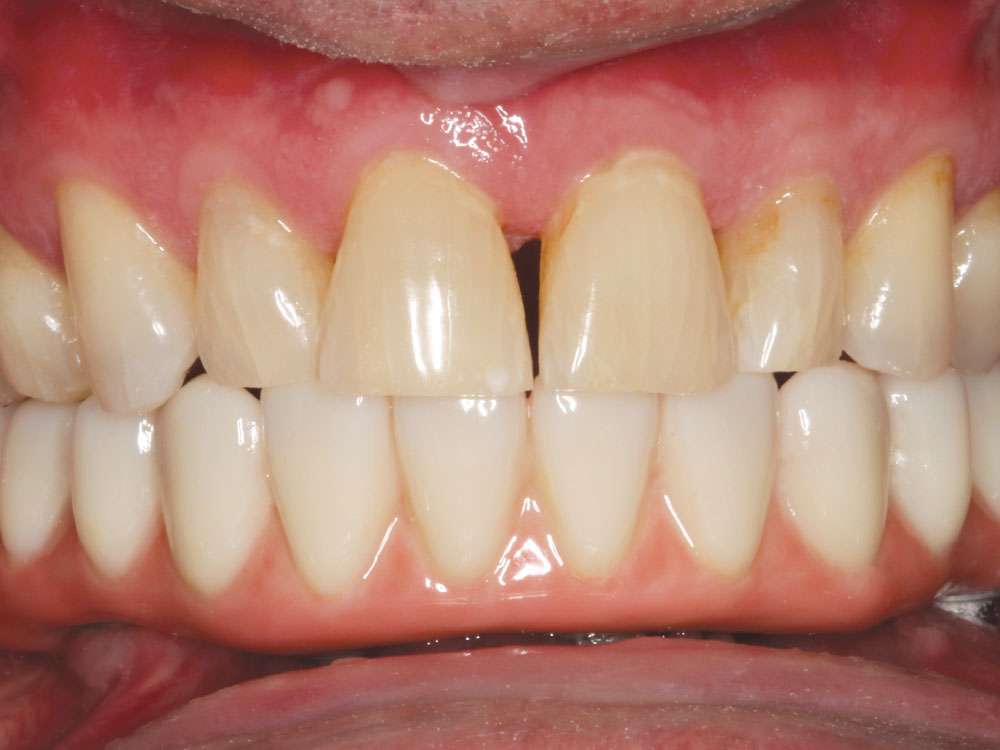

Dr. Fish recently placed five mandibular implants for a patient who requested a permanent solution for terminal dentition. He opted to place and immediately load five Hahn Tapered Implants with a fixed provisional denture. After the implant sites healed, Hahn Multi-Unit Abutments were connected to the implants and elevated the restorative platform above the soft tissue, thereby simplifying the fabrication of the immediate provisional denture as well as the final restoration.

JF: Sure. He had been a regular patient of mine for a number of years, and his lower teeth were failing at a pretty rapid rate due to periodontal disease. So we talked about all the options, and he finally decided it was time to move forward with replacing his terminal dentition. The patient had some esthetic and functional concerns, so a fixed implant restoration fabricated from BruxZir Zirconia was an ideal solution. He’s a huge guy — a bodybuilder, in fact — so the high strength and durability of monolithic zirconia was also important.

Prior to the surgical appointment, we had a temporary denture specifically made for conversion to a fixed appliance after placing implants. We took out his remaining lower teeth and immediately placed five Hahn™ Tapered Implants (Glidewell; Irvine, Calif.). I positioned the three anterior implants axially, and I angled the posterior implants mesially to avoid the inferior alveolar canal. I freehanded the surgical procedure, and it came out really well. We connected three straight multi-unit abutments to the anterior implants and two angled 17-degree multi-unit abutments to the posterior implants. Then, we prepared holes in the denture, did the pickup procedure with the temporary cylinders, reshaped it, and sent him home with the fixed, converted denture in place. This was my first immediate load fixed full-arch restoration on multi-unit abutments. As I mentioned earlier, this was a procedure I learned at Dr. Patel’s course at Glidewell. It was something I took home with me and was able to put it into practice within a few weeks. The patient is kind of a quiet guy, but it was obvious that he was really happy to leave there with fixed teeth.